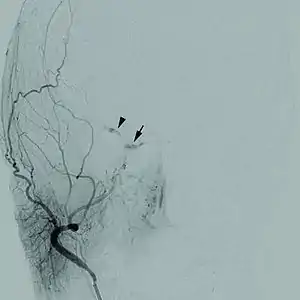

Cerebral angiogram of a carotid-cavernous fistula